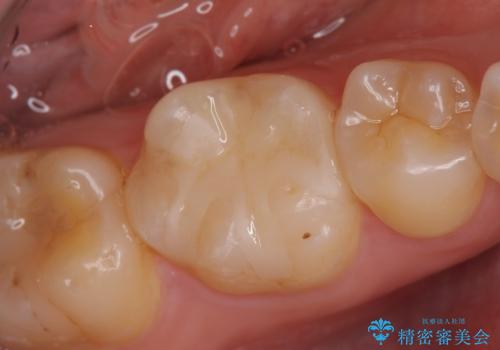

- 右上の銀歯を白くしたいといらっしゃった方の症例です。

右上4、5番目の歯はオールセラミッククラウンによる補綴、6番目の歯はセラミックインレーによる修復を行いました。

今回用いたオールセラミッククラウンは、ジルコニアフレームという白い素材の上にセラミックを盛っているため審美性が非常に高いのが特徴です。

またジルコニアは人工ダイヤモンドの材料にも使われているほど高い強度を持っており、そのためオールセラミッククラウンは審美性だけでなく、奥歯やブリッジの補綴も可能とするクラウンです。